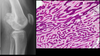

Histologia

Rico em matriz osteóide. Núcleos amorfos e hipercromáticos. Mitose anômala.

RX:

↳ Esclerose

↳ Metáfise

↳ Bordas irregulares

↳ Destruição cortical

↳ Reação periosteal - Triangulo de codman e Lamelar principalmente

RX:

Lesão esclerótica, aderida ao osso.

Similar ao Osteocondroma, porém a medular não é contígua na RNM.

Histologia:

Trabeculado ósseo similar ao normal, intermeado com fibrose.